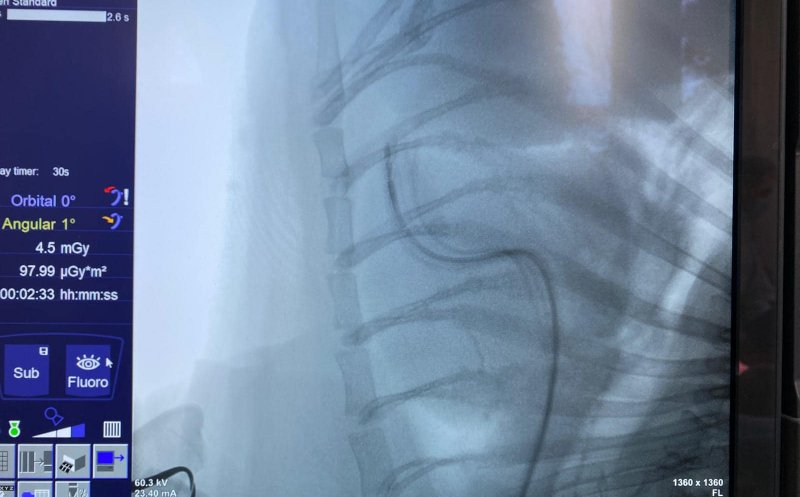

O intervenție medicală în premieră a avut loc la Facultatea de Medicină Veterinară din cadrul Universității de Științe Agricole și Medicină Veterinară (USAMV) Cluj-Napoca, unde a fost implantat, pentru prima dată, un stimulator cardiac unui pacient canin.

Operația a fost realizată cu succes de o echipă mixtă formată din Prof. dr. Iuliu Scurtu, coordonatorul Serviciului de Cardiologie Veterinară, și Conf. dr. Horia Roșianu, medic primar cardiolog la Institutul Inimii „Niculae Stăncioiu” și cadru didactic la UMF „Iuliu Hațieganu”.

Pacientul, un buldog pe nume Arni, suferea de multiple episoade zilnice de leșin, cauzate de tulburări severe de ritm cardiac. Implantarea stimulatorului a fost soluția salvatoare, iar intervenția reușită marchează un pas important în colaborarea dintre medicina veterinară și cea umană.

„Împreună cu Dr. Roșianu am implantat cu succes la clinica noastră un stimulator cardiac la un pacient care prezenta zilnic multiple episoade de leșin. Operația a fost un succes și este o premieră. Tocmai a început o viață nouă pentru simpaticul buldog Arni!”, a declarat Prof. dr. Iuliu Scurtu.